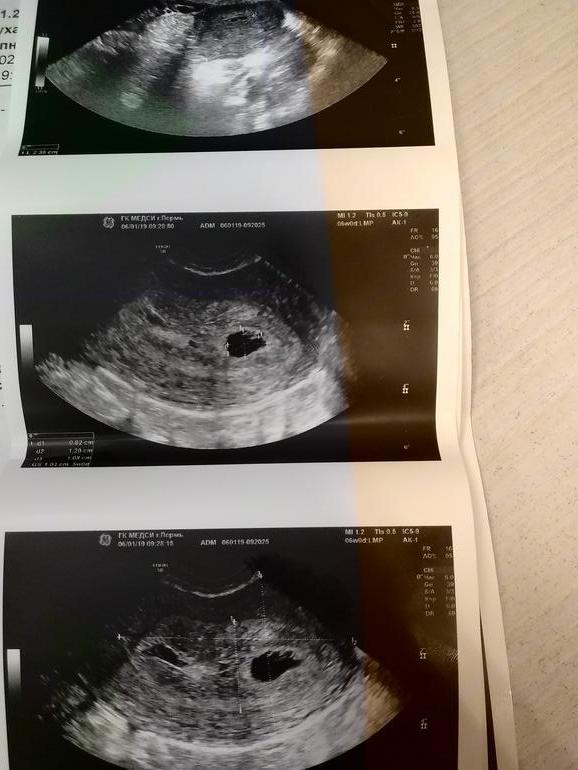

ФолликулометрияДевочки, пишу и плачу ((( так была рада увидеть две полоски перед новым годом, сходила на узи сегодня, первый день последних месячных 25 ноября, эмбриона не нашли, по месячным 6 недель. Это всё? ХГЧ пойду сдавать на днях

Тихо, Тихо, ну что вы? все будет хорошо, вам сказали что у вас одноицовые близнецы??скорей всего, появится куда они денутся, желчный мешочек есть, значит и бусеньки прячутся!! Удачи вам!! ПЯ размер я так и не поняла??!!

Я тоже не поняла из результатов (( может она определить это не смогла, сказала что он должен быть ровным пя, а у меня какой то неровный

У вас написано перегородка, а диаметр ПЯ нет, подождите немного дней 5, мы ждём от вас новостей!! Я честно сама на нервах вся первый скрининг 9 января очень баюсь, так что не переживайте, у вас всё будет хорошо!!

Меня смущают перегородки и камеры, что их несколько. Рано я радовалась. Быстрее бы уже сдать ХГЧ и картина станет яснее